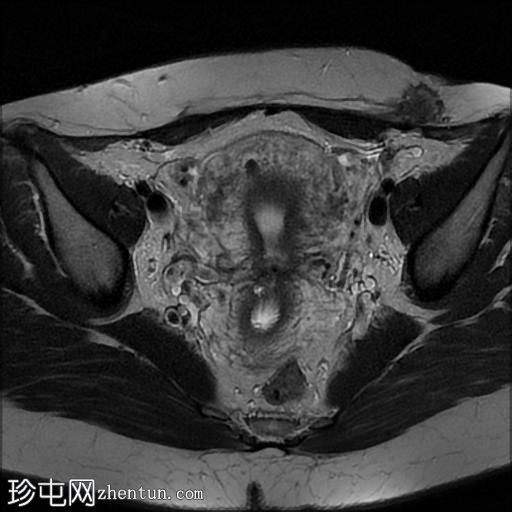

轴位

T2加权像

左侧腹直肌和腹内斜肌前缘旁可见一边界不清的深部皮下软组织肿块。T1加权像呈等信号,T2加权像呈中低信号,增强扫描呈中度不均匀强化。

可见微小的肌壁内平滑肌瘤。

未见卵巢或腹膜下子宫内膜异位症。

临床表现和MRI特征最符合剖宫产瘢痕子宫内膜异位症。